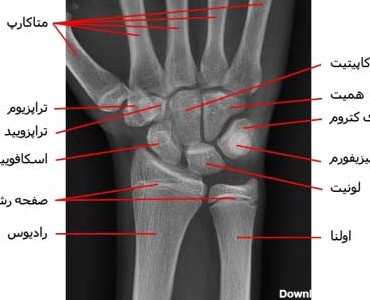

آناتومی استخوان ها و مفاصل مچ دست چیست، آناتومی استخوان های مچ دست چگونه است، تشریح استخوان و مفصل مچ دست

همه چیز درباره آناتومی مچ دست، عصبهای دست کدامند؟ چه بیماریهایی مربوط به مچ دست میباشد، آناتومی مچ دست شامل چه قسمتهایی است؟